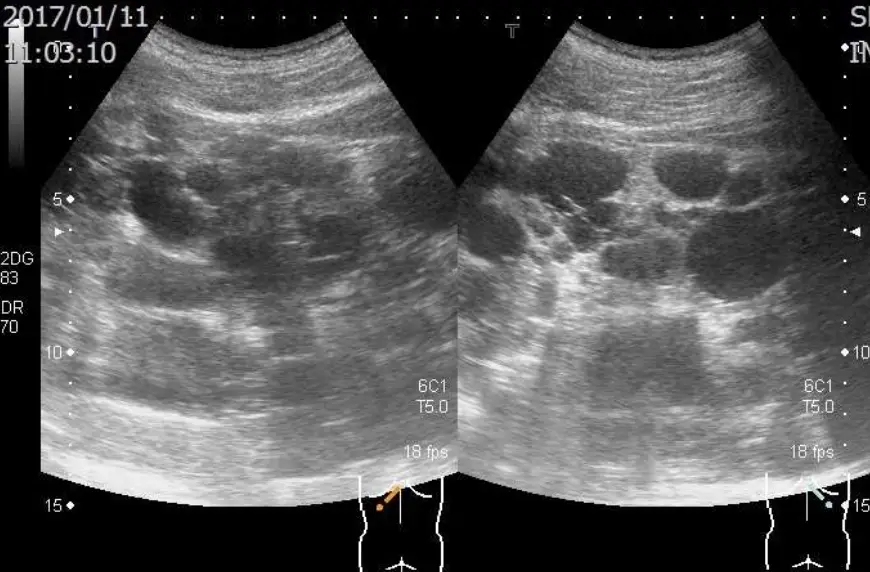

某45歲男性已有高血壓5年,最近檢查有血尿RBC 10-20/HPF、Cre 1.2 mg/dL、超音波檢查發現兩側腎臟長徑超過15公分(如圖)及各有囊腫數目超過十個;家族史為父親自60歲開始血液透析,不曾顱內出血,父親的腎臟超音波亦有雷同的發現。 請問關於其腎臟疾病之敘述,下列何者為正確?(1)每年定期追蹤腎功能,即為預估日後是否需要透析治療之最敏感方法;(2)若其太太懷孕可做產前篩檢,其子女遺傳此腎臟疾病的機會為50%;(3) 以影像學檢查估算其腎臟體積,若超過600立方公分,其腎功能極可能持續逐年惡化;(4) 雖無症狀,應每年安排腦部血管Magnetic resonance angiography的檢查;(5)宜建議停止服用含女性荷爾蒙之避孕藥。

超音波顯示雙側腎臟顯著腫大,長徑均超過15公分,皮質下及實質散在多發性囊腫,每側囊腫數量逾十顆,為 ADPKD 的典型表現。腎臟體積持續增大與未來 GFR 下降密切相關,影像量化可作為早期預測工具。